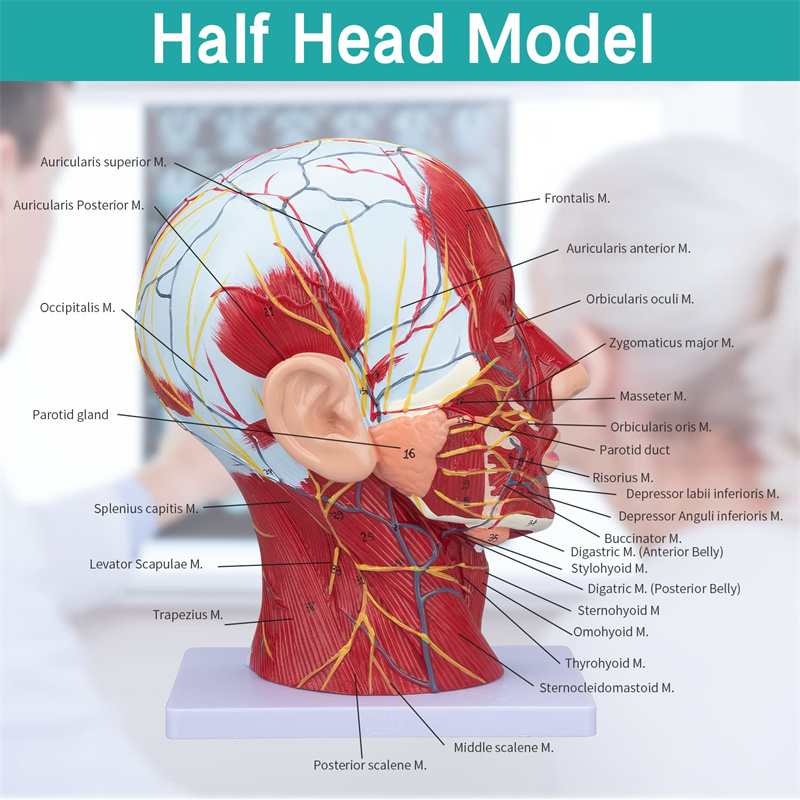

| פֿעיִקייטן | דער מאָדעל ווייזט די היגע מאָרפאַלאַדזשי פון די ינער און ויסווייניקסט זייטן פון די מידיאַן סאַגיטטאַל אָפּטיילונג פון די קאָפּ און האַלדז, און די סטראַקטשערז פון בלוט כלים און נערוועס און עס זענען 84 פּאַרץ ינדאַקייטינג וואונדער אין גאַנץ. |

【Superficial Neurovascular Muscle Model】Highly detailed, numbers marked, detachable ear, deepen the understanding of the superficial muscles, vessels, nerves and the internal structures of the head & neck. רויט-אַרטעריע, בלוי-אָדער, געל-נערוו.

【פֿעיִקייטן】 עס געוויזן די אויבנאויפיקער מאַסאַלז פון די יקספּאָוזד פּנים; די אויבנאויפיקער בלוט כלים & נערוועס פון די פּנים & סקאַלפּ; די ינער סטראַקטשערז פון פּאַראָטיד דריז & אויבערשטער רעספּעראַטאָרי שעטעך; די סאַגיטטאַל קרייַז-אָפּטיילונג סטרוקטור פון די סערוואַקאַל רוקנביין.

דער מאָדעל ווייַזן דעטאַילס פון די רעכט קאָפּ האַלדז און מיטן סאַגיטטאַל אָפּטיילונג פון דער מענטש. אַרייַנגערעכנט די אויבנאויפיקער

מאַסאַלז פון די יקספּאָוזד פּנים; די אויבנאויפיקער בלוט כלים און נערוועס פון די פּנים און סקאַלפּ; די ינער סטראַקטשערז

פון פּאַראָטיל דריז און אויבערשטער רעספּעראַטאָרי שעטעך; די סאַגיטטאַל קרייַז-אָפּטיילונג סטרוקטור פון די סערוואַקאַל רוקנביין.

דער מאָדעל געוויזן די היגע מאָרפאַלאַדזשי פון די מעדיאַל און לאַטעראַל סאַגיטטאַל סעקשאַנז פון די קאָפּ און האַלדז און די וואַסקיאַלער און נערוו סטראַקטשערז, מיט אַ גאַנץ פון 100 פּלאַץ ינדאַקייטערז.